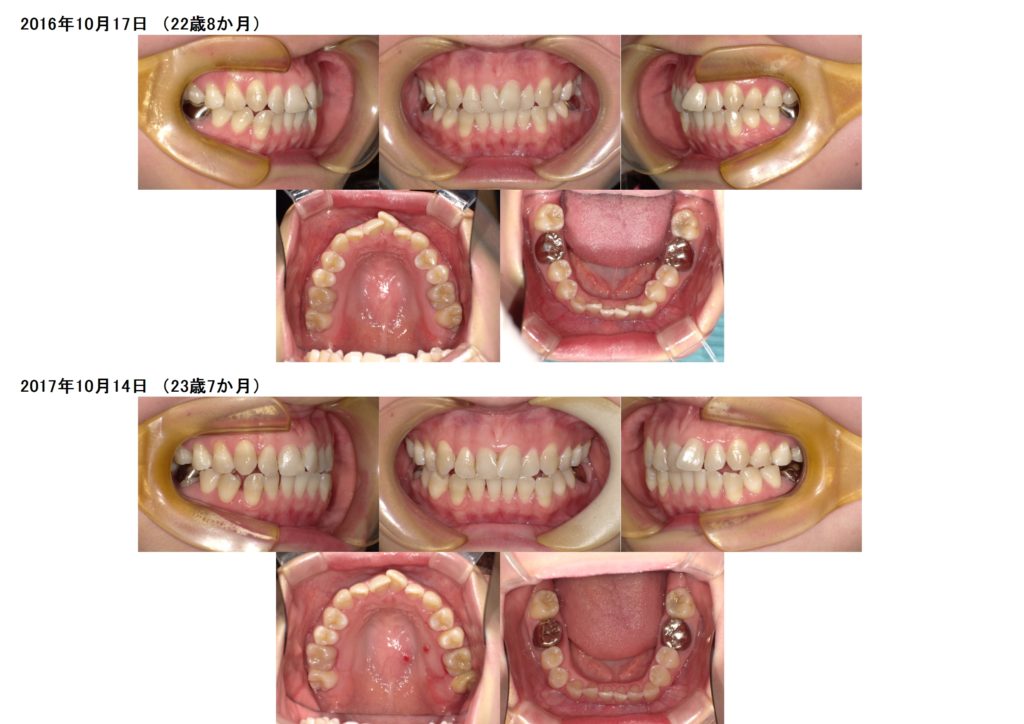

↑上下の写真を見比べると、歯と歯の間にすき間が取れているのが分かります。

奥歯の位置も変わっていたりします。簡単に言うと、顎を広げます。これはお顔が大きくなるわけではないのでご心配なく!!

広げるといっても、その方の骨格に対して理想的な数値にするので、整っている状態になります。

アンカースクリューを使用し、この患者様は遠心移動を行いました。

奥に歯を移動させる治療方法です。

このように、しっかりとスペースが取れたら、インビザラインに移行します。